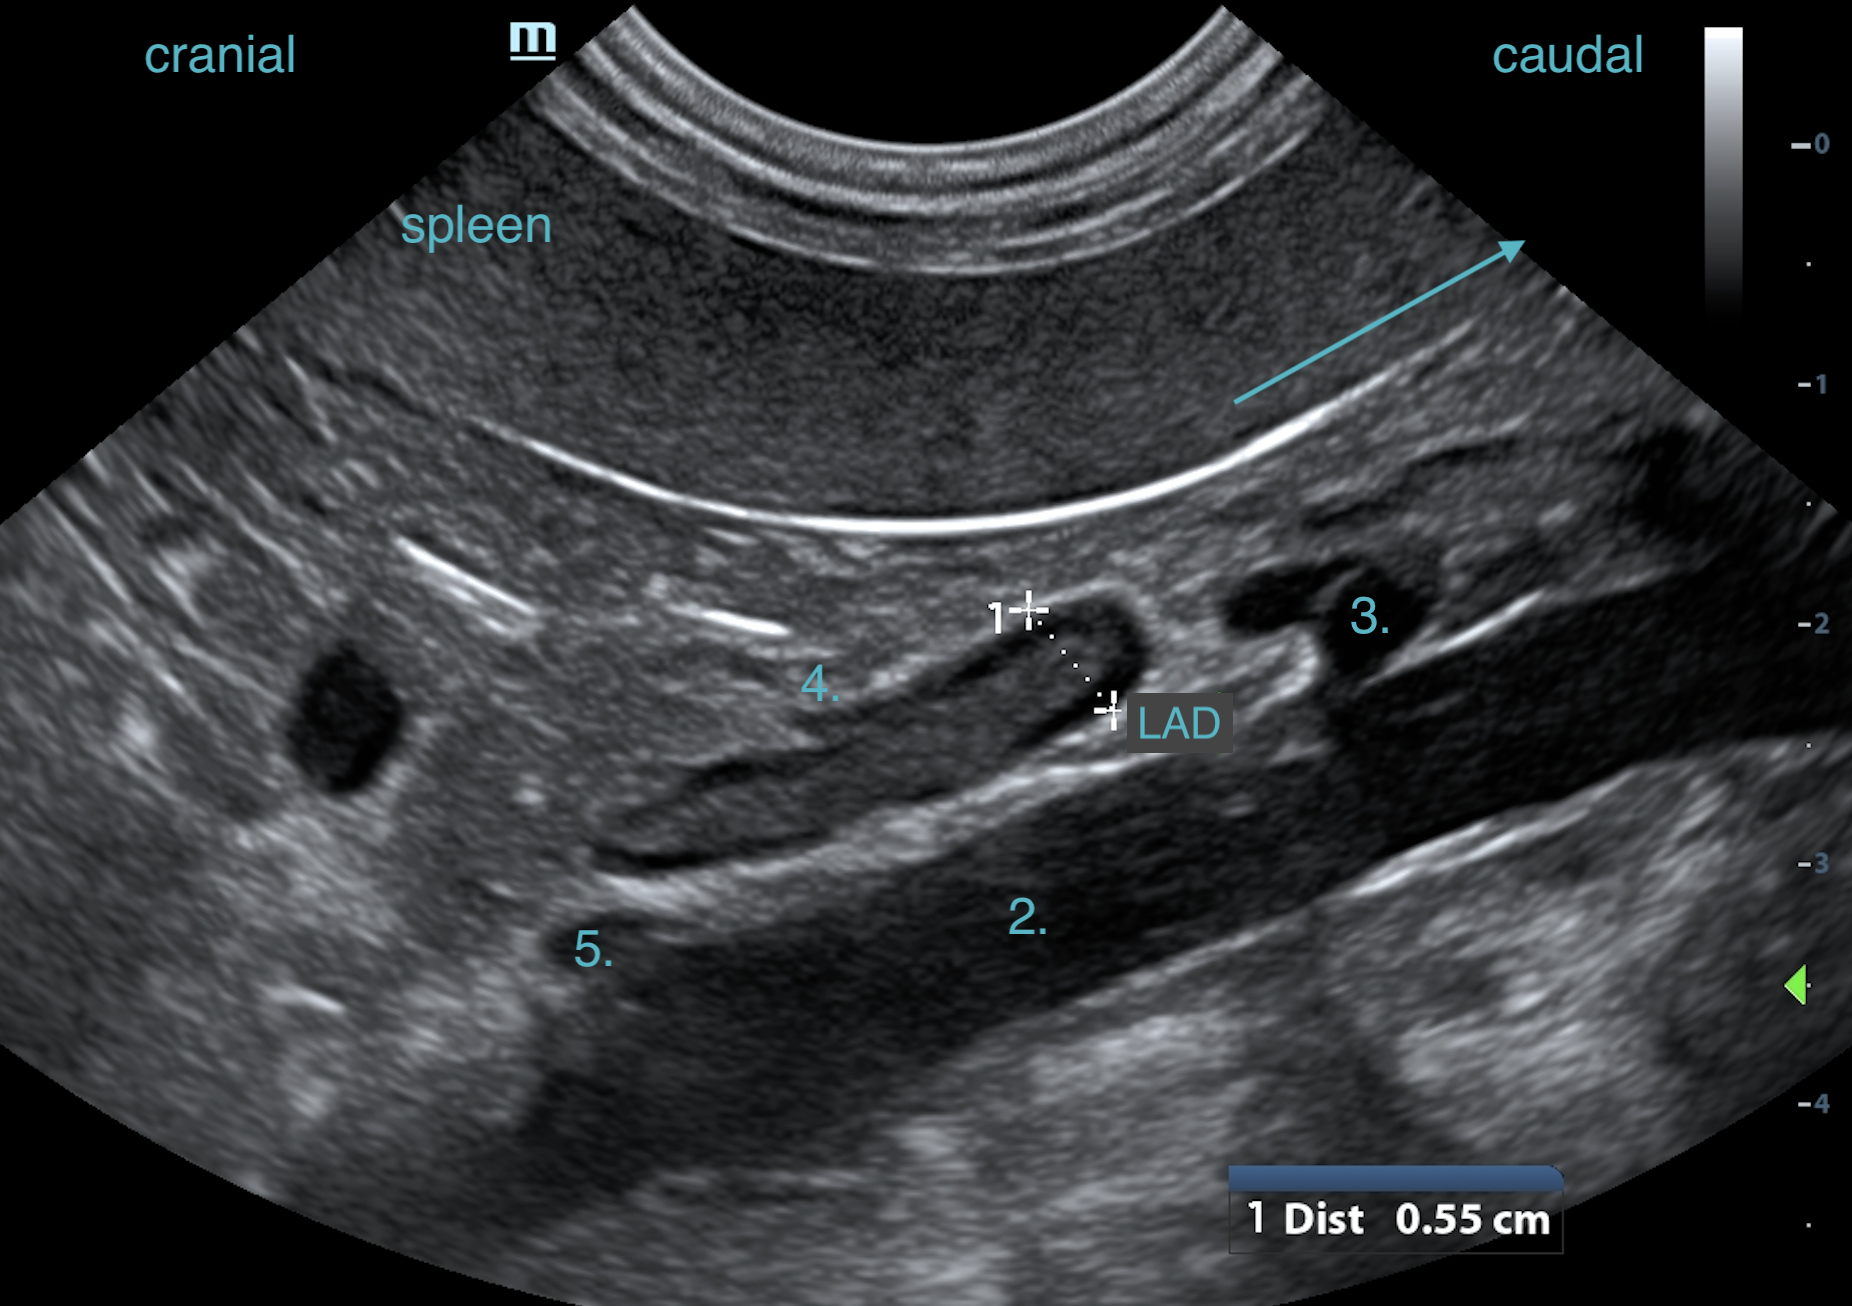

• Recognise normal vs abnormal with clarity

3. How to interpret what you’re seeing in real life scans

• Normal adrenal appearance and measurements

• Common abnormalities + differentials explained simply